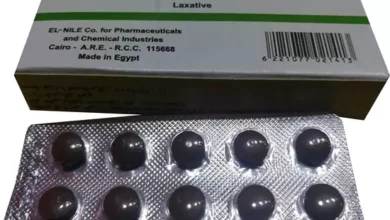

أسباب استخدام سنا لاكس والأعراض سعر المنتج والجرعات المناسبة واهم البدائل له

يعد سينالاكس من العلاجات الفعالة لمعالجة الإمساك الوظيفي المزمن، وذلك لأنه يحفز القولون بشكل سريع وفعال، حيث يبدأ مفعوله لفترة…